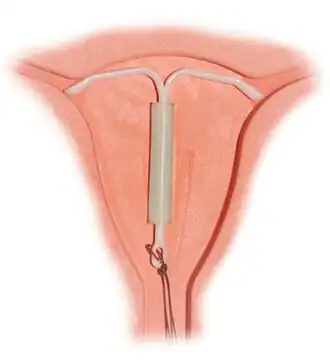

Most copper IUDs have a T-shaped frame that is wound around with pure electrolytic copper wire and/or have copper collars (sleeves). The arms of the frame hold the IUD in place near the top of the uterus. The Paragard TCu 380a measures 32 mm (1.26") horizontally (top of the T), and 36 mm (1.42") vertically (leg of the T). Copper IUDs have a first-year failure rate ranging from 0.1 to 2.2%.[46] They work by damaging sperm and disrupting their motility so that they are not able to fertilize an egg. Specifically, copper acts as a spermicide within the uterus by increasing levels of copper ions, prostaglandins, and white blood cells within the uterine and tubal fluids.[6][47] The increased copper ions in the cervical mucus inhibit the sperm's motility and viability, preventing sperm from traveling through the cervical mucus, or destroying it as it passes through.[48] Copper can also alter the endometrial lining, and while studies show that this alteration can prevent implantation of a fertilized egg ("blastocyst"), it cannot disrupt one that has already been implanted.[49]

Hormonal

Hormonal IUDs (referred to as intrauterine systems in the UK) work by releasing a small amount of levonorgestrel, a progestin. Each type varies in size, amount of levonorgestrel released, and duration. The primary mechanism of action is making the inside of the uterus uninhabitable for sperm.[58] They can also thin the endometrial lining and potentially impair implantation, but this is not their usual function.[59][60] Because they thin the endometrial lining, they can also reduce or even prevent menstrual bleeding. As a result, they are used to treat menorrhagia (heavy menses), once pathologic causes of menorrhagia (such as uterine polyps) have been ruled out.[61] In a 10-year study, the levonorgestrel coil was found to be as effective as oral medicines (tranexamic acid, mefenamic acid, combined oestrogen–progestogen or progesterone alone); the same proportion of women had not had surgery for heavy bleeding and had similar improvements in their quality of life.[62][63]

The progestin released by hormonal IUDs primarily acts locally; use of Mirena results in much lower systemic progestin levels than other very-low-dose progestogen only contraceptives.[64]